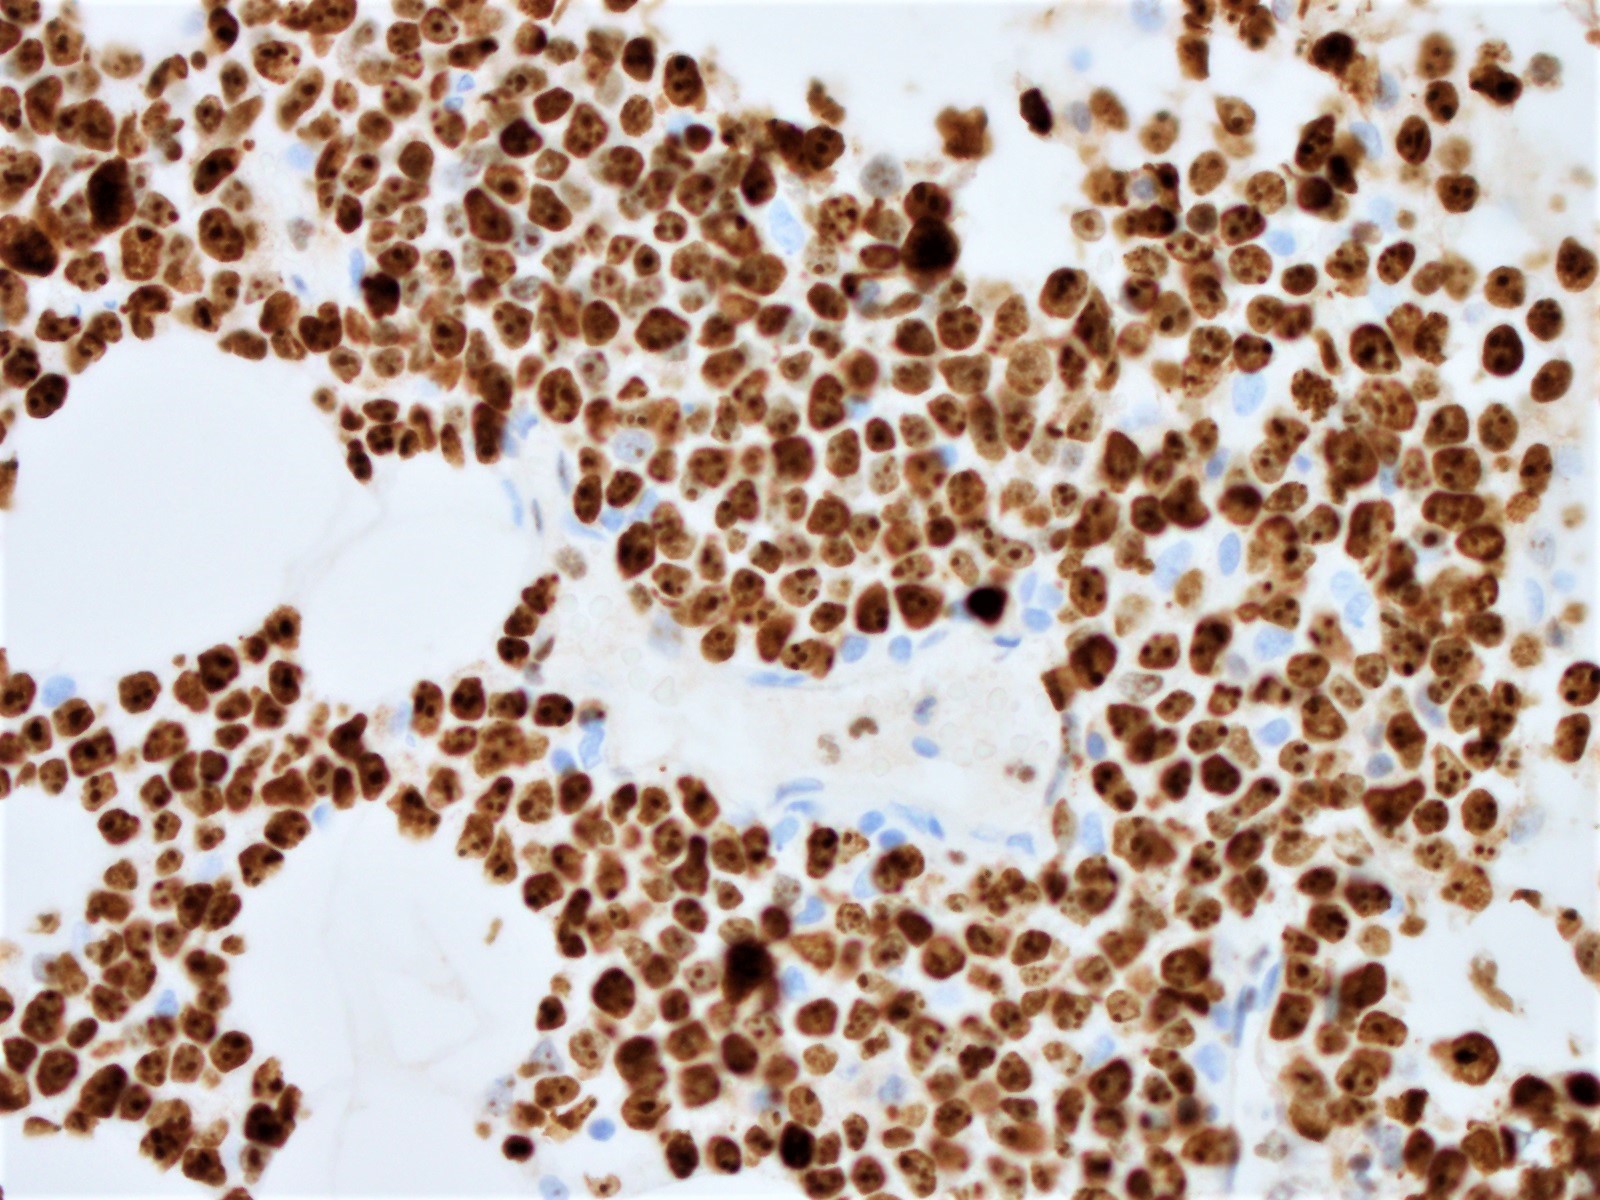

Microscopic (histologic) images

Positive stains

- Ki67 count (J Hematop 2009;2:103)

- Five independent high power fields count

- Avoidance of residual germinal centers, hot spots and proliferating T cells

- Note: Ki67 index is not sufficient to classify as blastoid or pleomorphic subtype

- Classical mantle cell lymphoma might also show high cell proliferation (Blood 2008;111:2385)